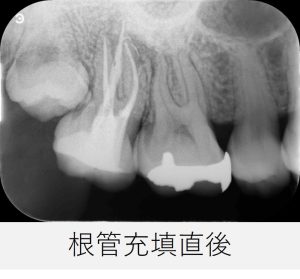

▲根管充填直後のレントゲン画像

根の形が曲がっている部分まで、しっかりと材料が充填されています。